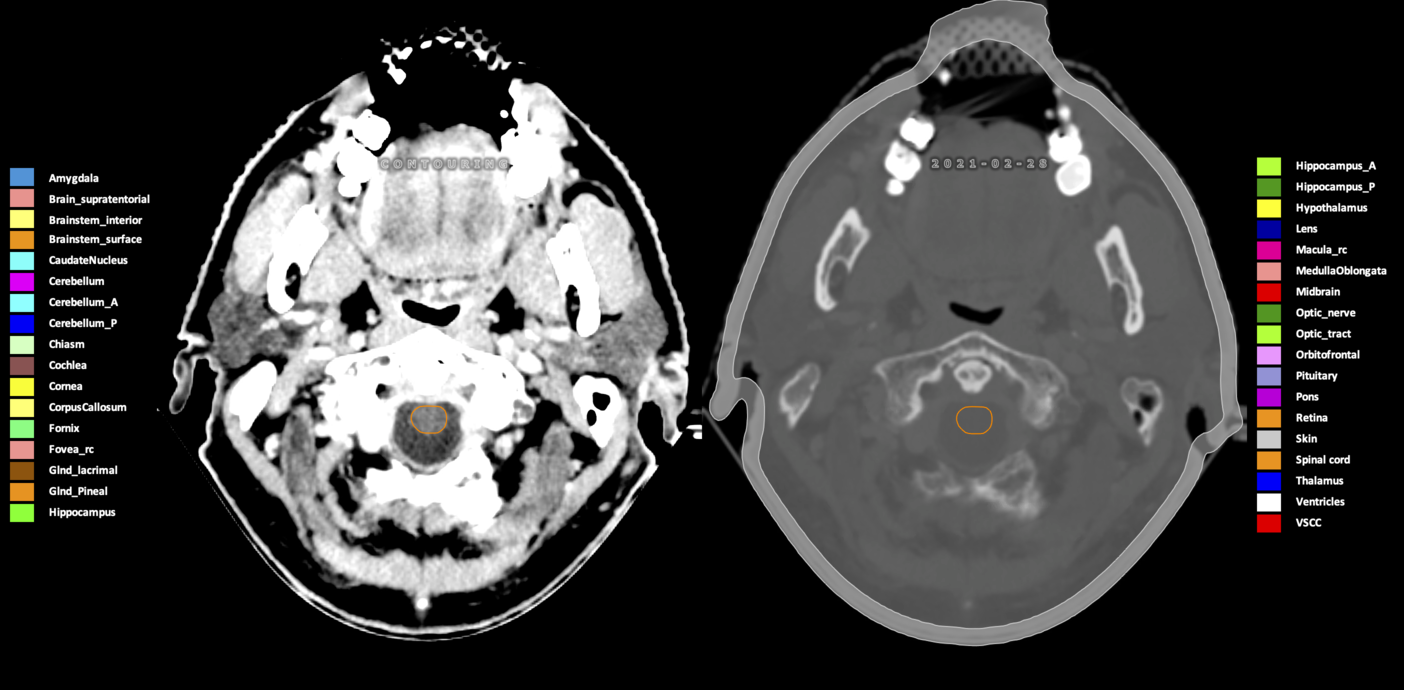

Included are all OARs known to be relevant for radiation-induced toxicity in neuro-oncology: brain, brainstem (midbrain, pons, medulla oblongata), chiasm, cerebellum (anterior & posterior), cochlea, cornea, hippocampus (anterior & posterior), hypothalamus, lens, lacrimal gland, optic nerve, pituitary, skin, and vestibular & semicircular canals. To further facilitate research on cognition, vision and radiological changes after irradiation of the brain, potential clinically-relevant OARs are included: amygdala, caudate nucleus, cerebellum (anterior & posterior), corpus callosum, fornix, macula, optic tract, orbitofrontal cortex, periventricular space (PVS), pineal gland, and thalamus.

Three-dimensional delineation of the 25 consensus OARs for neuro-oncology are shown on CT (WW/WL 120/40, 3000/600), 3T MR images, (T1Gd, T2FLAIR 1mm) and 7T MR (MP2RAGE 0.7 mm). All are presented in transversal, sagittal and coronal view.